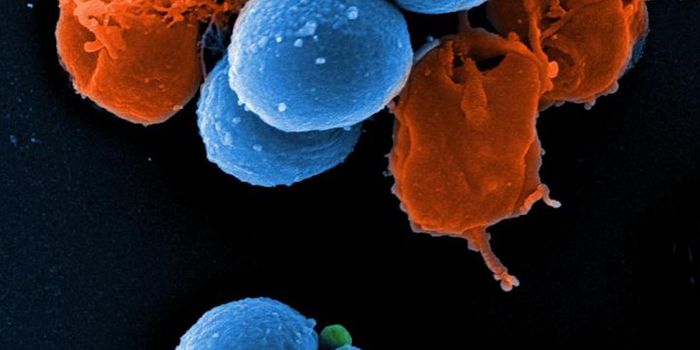

SEP 17, 2021Cell & Molecular BiologyMRSA (methicillin-resistant Staphylococcus aureus) is a well known superbug, a pathogenic microbe that can cause serious ...